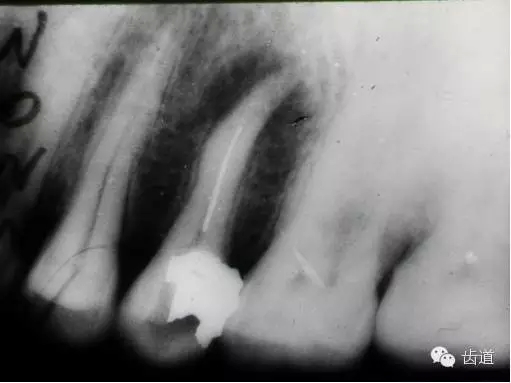

左上5牙頸部側(cè)穿

開(kāi)髓時(shí)鉆針進(jìn)入方向與根管走行方向不一致,鉆針需改變方向時(shí)。

牙長(zhǎng)軸傾斜,在傾斜方向的髓腔壁易穿孔

根管壁穿孔多在根管彎曲處。

左上4鑄造樁側(cè)穿